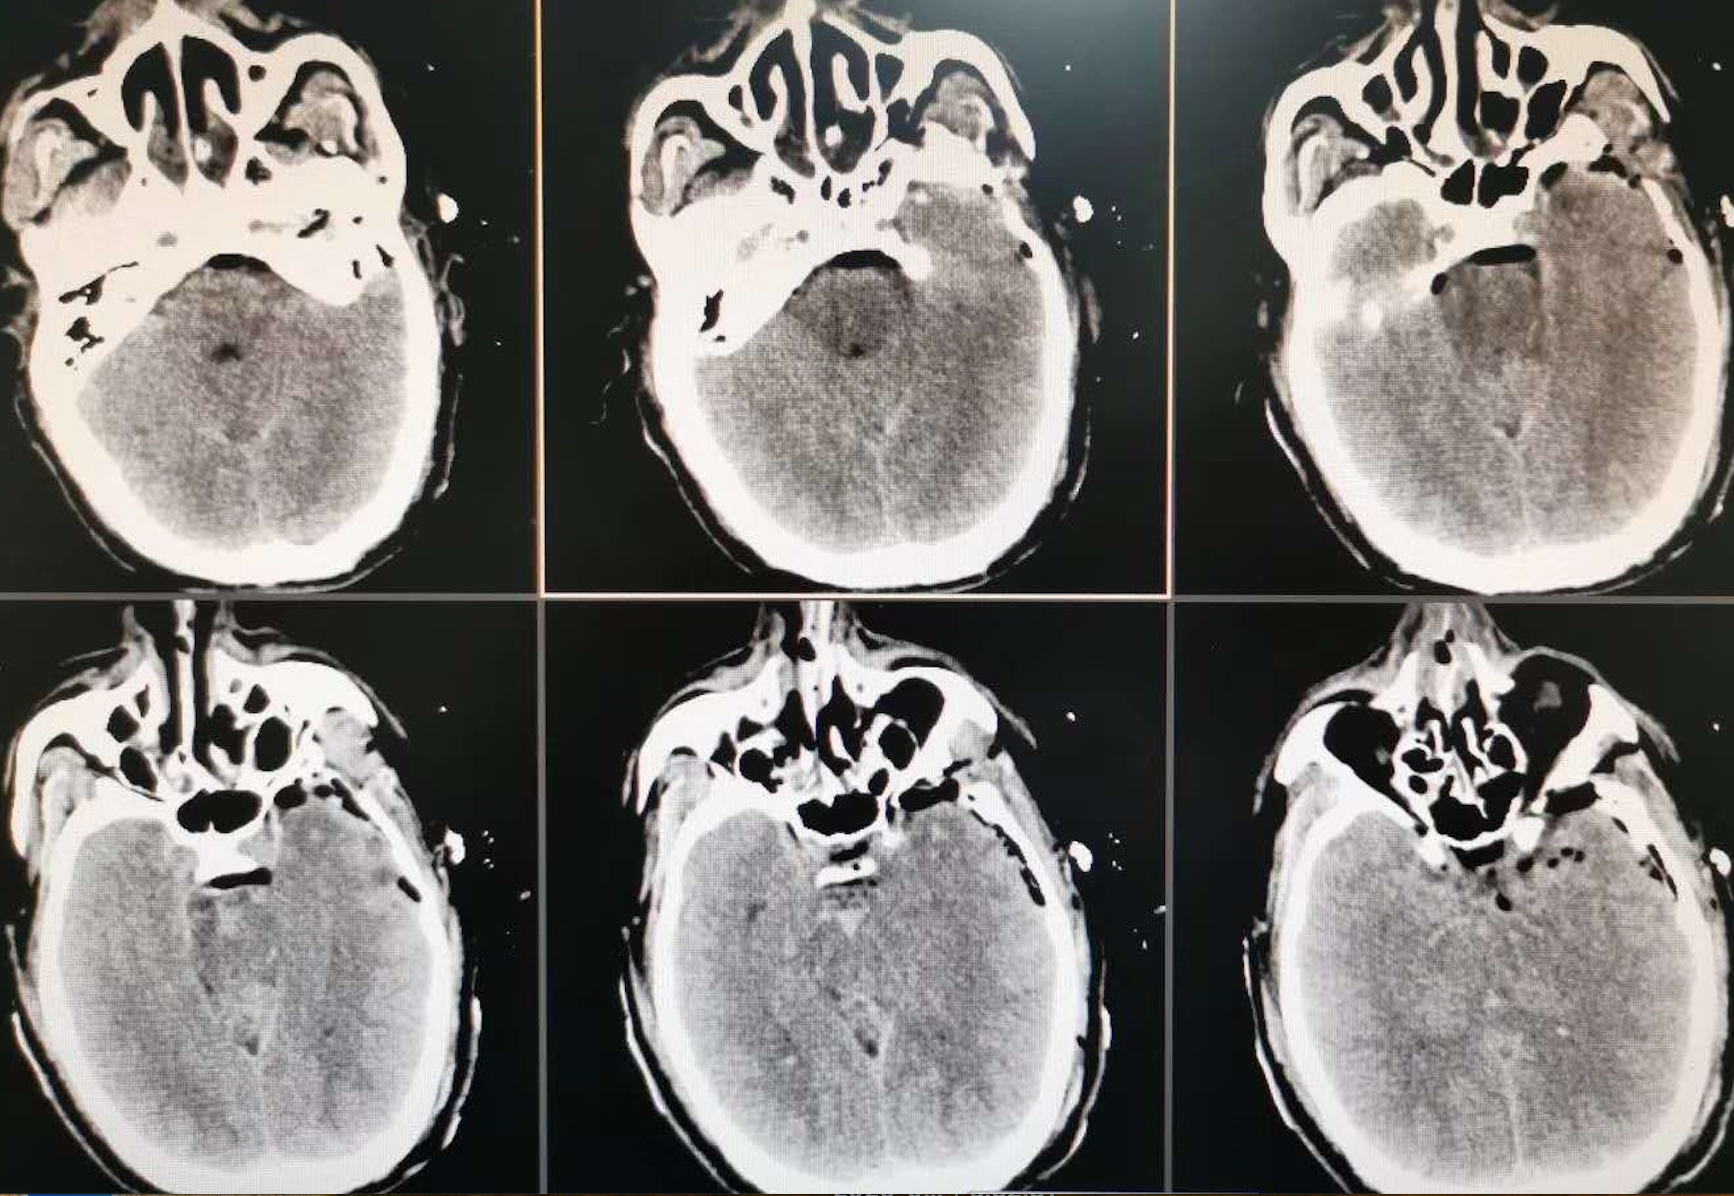

术前影像

颅内动脉瘤的精准夹闭